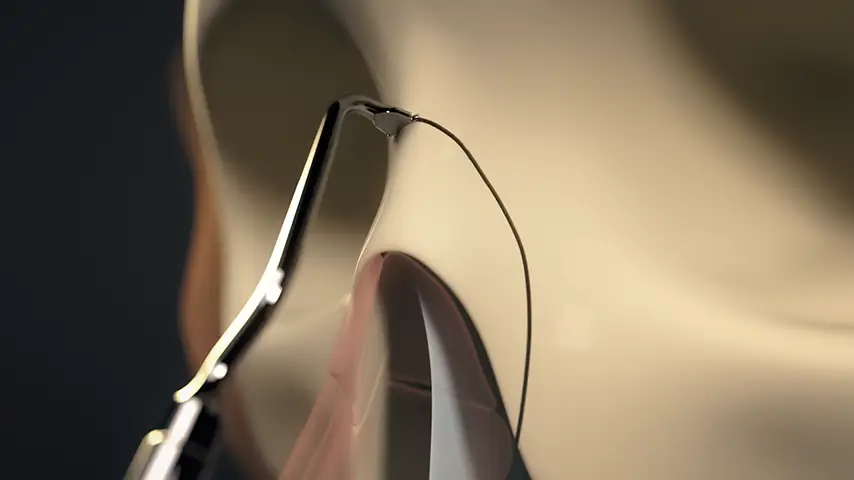

Lateral osteotomy of nasal bone

Transverse osteotomy of nasal bone

Drilling of septum for suture fixation

Details

The finest and angled insert for insertion in limited space;

ideal for perforating nasal bones as well as ethmoid lamina splints.

Recommended insert: